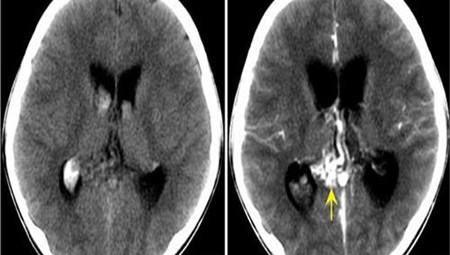

肾积水多是指的尿路梗阻时,肾脏分泌的尿液无法排除最终积聚在肾脏内,随着时间的推移,慢慢导致肾盂扩张也就是肾积水。早期的肾积水并不用过于担心,只要治疗及时很快就好,但如果放任不管,肾积水严重的话会成肾盂、肾盏内压力上升影响肾脏功能。

肾积水也可以算是肾盂分离数值逐渐增加的后果,尤其胎儿发生肾积水的原因较为复杂,主要分为可复性即胎儿发育过程中出现肾功能失常或者结构异常,另一种不可复性,往往常见于先天性的输尿管发育狭窄。